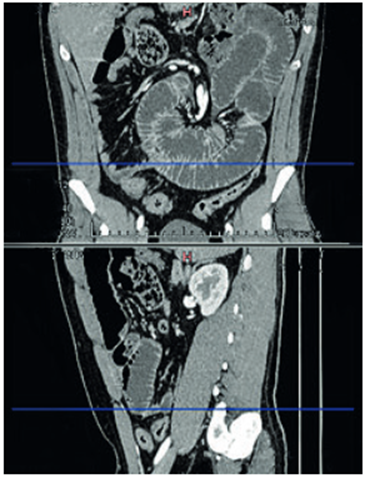

Paciente masculino de 28 años de edad, con antecedente de laparotomía exploratoria y resección intestinal por obstrucción intestinal al mes de vida. El paciente ingresó con cuadro de 12 horas de evolución de dolor abdominal, localizado en epigastrio, asociado a vómito. Al examen físico, los signos vitales eran normales, el abdomen distendido, doloroso a la palpación profunda en epigastrio e hipocondrio izquierdo. En el hemograma se encontró leucocitosis de 12.070 células por microlitro y neutrofilia de 84 %. Se realizó una tomografía computarizada de abdomen que informó distensión de asas de intestino delgado, con zona de transición a nivel del íleon terminal, compatible con obstrucción intestinal mecánica (posible brida intestinal) (Figura1).

Por lo anterior, el paciente fue diagnosticado con obstrucción intestinal por adherencias y se realizó una liberación de adherencias por laparoscopia. En el posoperatorio, el paciente se mantuvo con débitos altos por la sonda nasogástrica, por lo que al quinto día se solicitó un tránsito intestinal con gastrografina, sin existir progresión del contraste en el intestino delgado, con falta de vaciamiento gástrico (Figura 2).